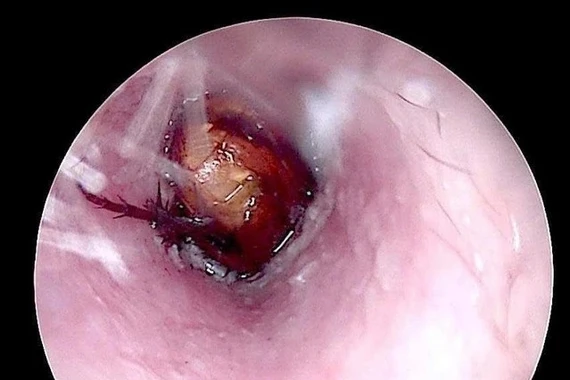

Qua thăm khám và chẩn đoán hình ảnh, các bác sĩ xác định dị vật là một đồng xu thép có đường kính khoảng 3 cm, nằm ở 1/3 dưới thực quản – vị trí tiềm ẩn nhiều nguy cơ nếu không được xử trí kịp thời.

22-gio-dem-1.jpg

Hình ảnh đồng xu trong thực quản trẻ - Ảnh BVCC